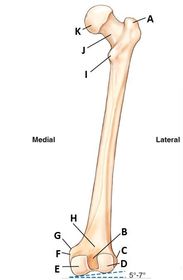

A. greater trochanter B. intercondylar fossa (notch) C. lateral epicondyle D. lateral condyle E. medial condyle F. medial epicondyle G. adductor tubercle H. popliteal surface I. lesser trochanter J. neck K. head